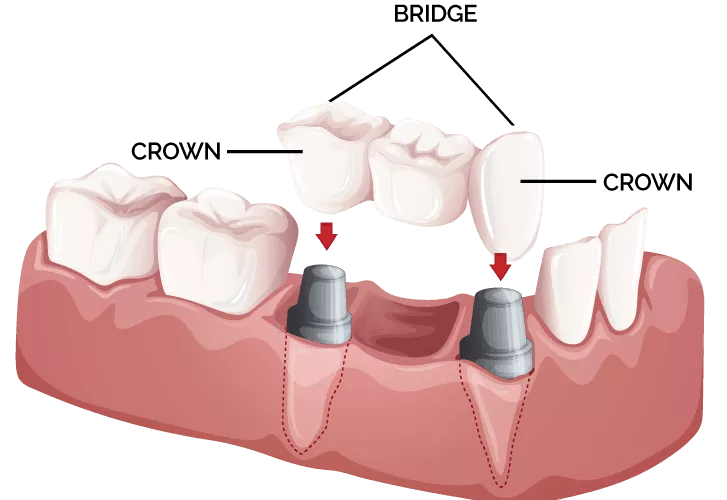

Dental crowns are caps placed over damaged or weakened teeth to restore their shape, size, and strength. They provide protection and improve the appearance of cracked, worn, or root canal-treated teeth.

Dental bridges, on the other hand, are used to fill gaps left by missing teeth. We custom design crowns and bridges using high-quality, tooth-colored materials to match your natural smile and restore proper bite alignment.